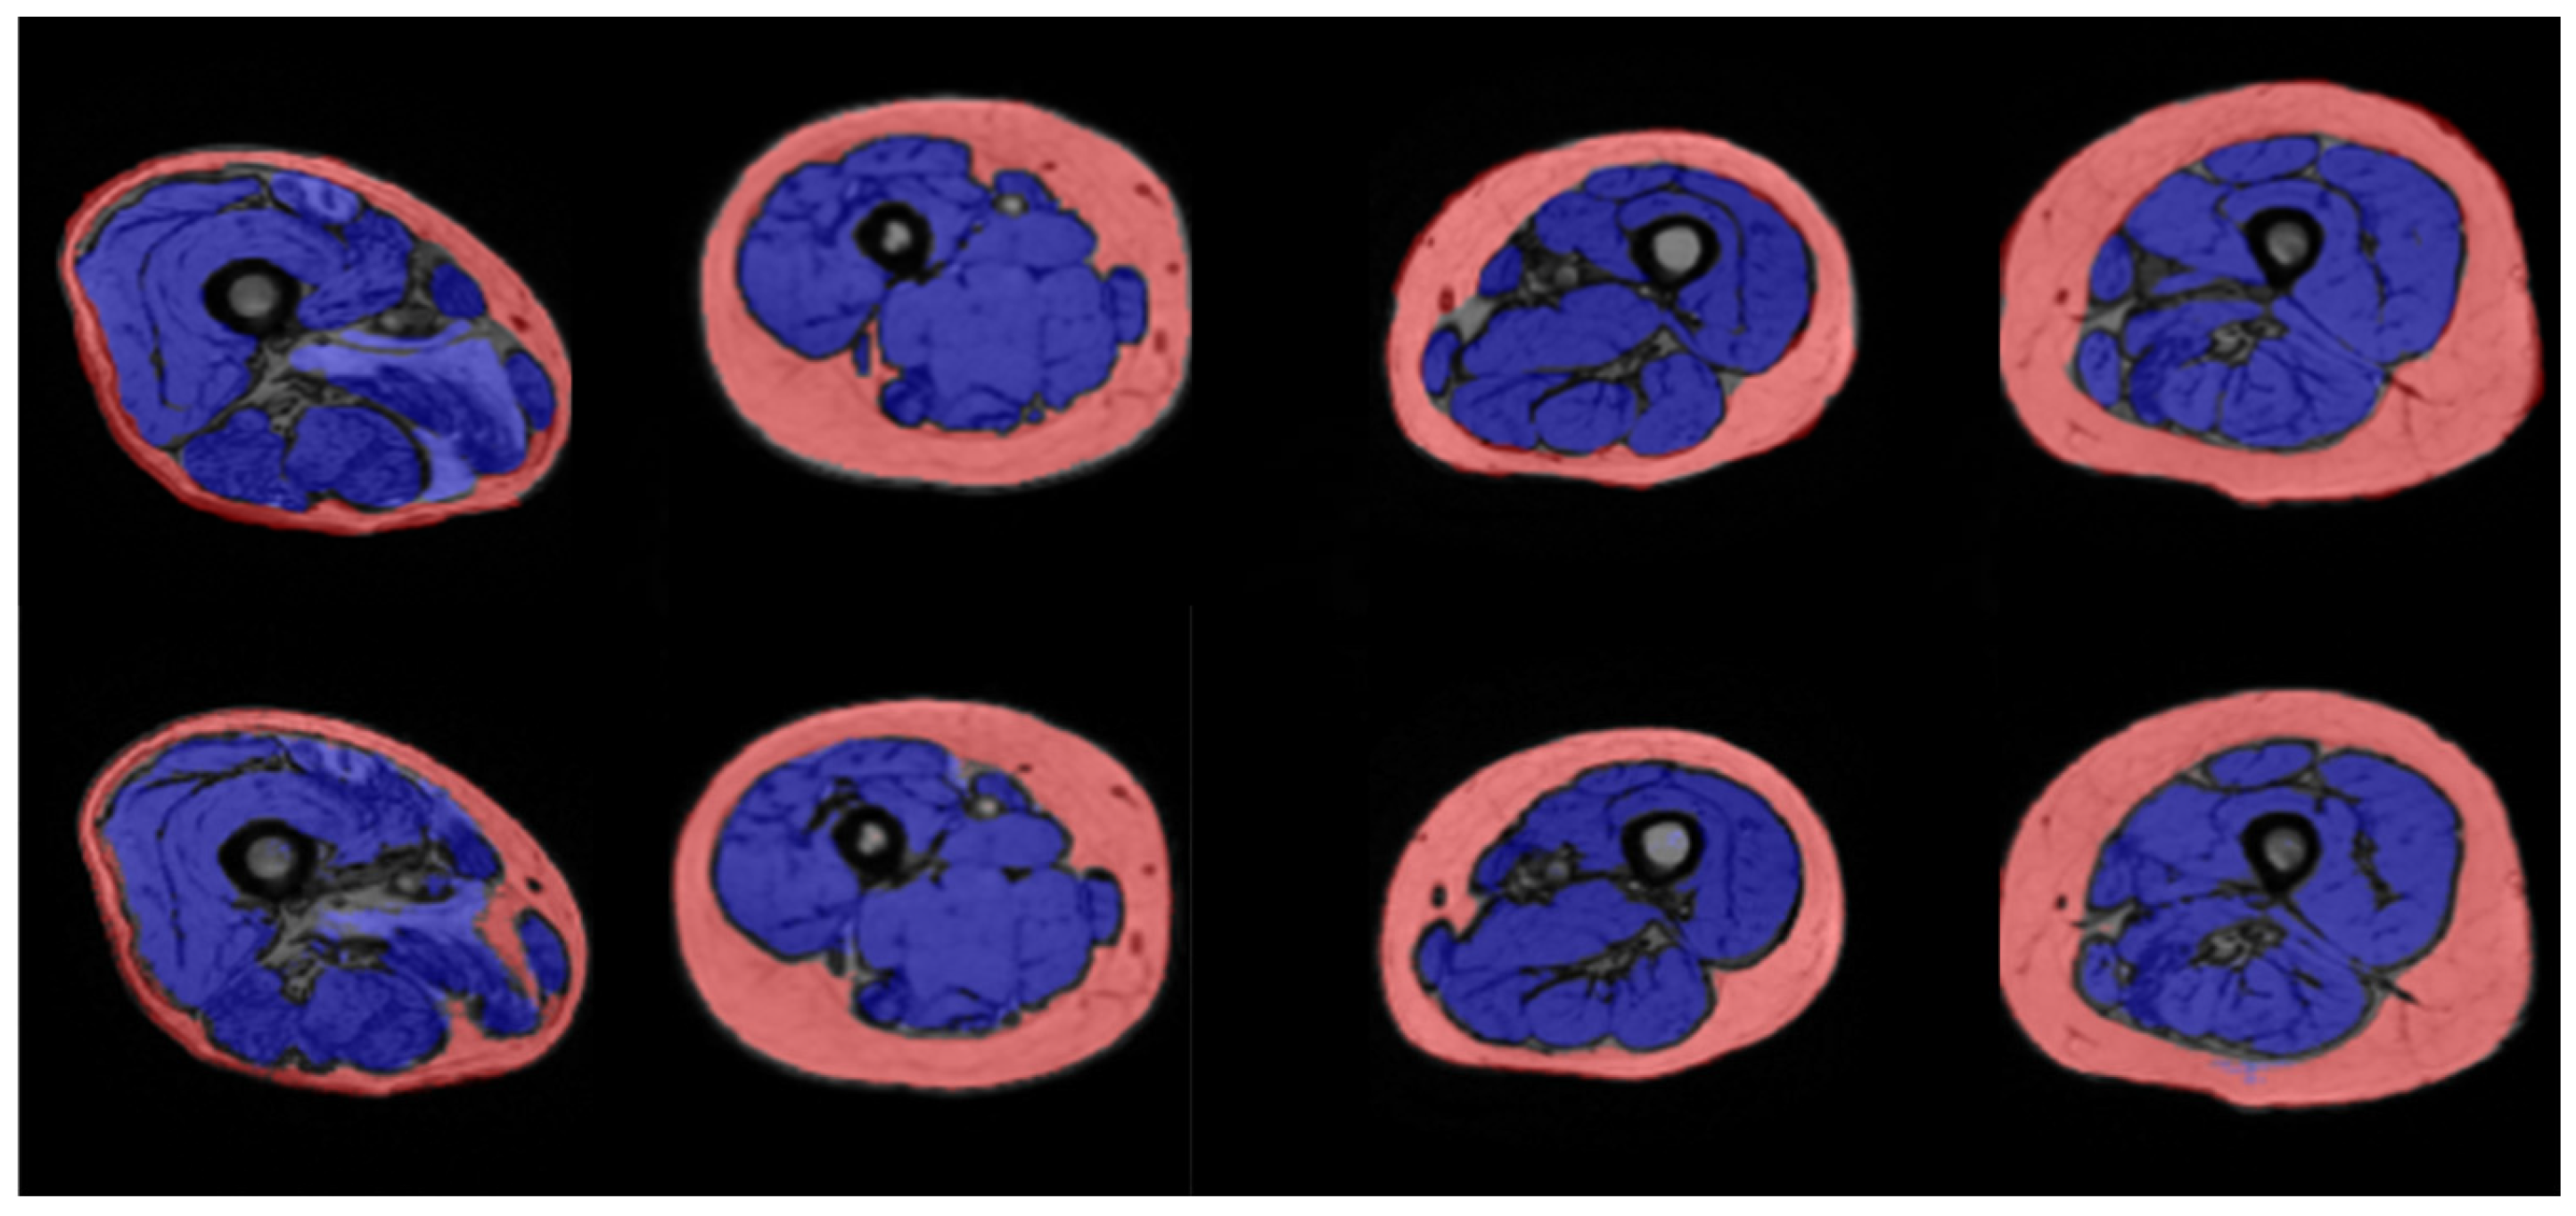

2.3. Manual Segmentation

2.5. Automatic Segmentation

3. Results